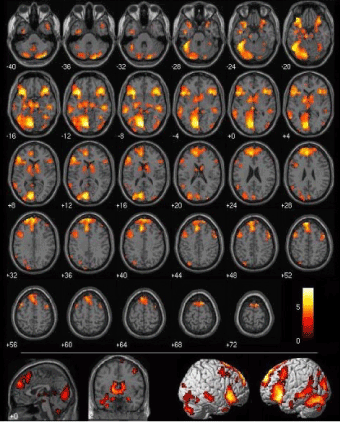

One technique currently used to determine anatomical alterations of the brain is the "Voxel-Based Morphometry" (VBM). This technique allows a comparison (voxel by voxel) of cerebral microstructures, with the possibility to detect and quantify the relationship between gray and white matter in a two-group comparison, starting from the elaboration of images in nuclear magnetic resonance. This technique has been used with success in the exploration of psychopathological conditions defined as functional by classical psychiatry. The evaluation uses a statistical approach known as "statistical parametric mapping (Figure 5)."

Figure 5. Voxel-Based Morphometry (VBM) results. (a) Negative correlation between gray matter volume in the right superior parietal lobe and offsite pointing accuracy. (b) Positive correlation between gray matter volume in the right hippocampus and offsite pointing accuracy. Note that the increase in gray matter is located in the tail of the right hippocampus. (c) Negative correlation between gray matter volume in the caudate (bilateral) and offsite pointing accuracy. Threshold in (a) is P < 0.05 corrected for multiple comparisons across the entire brain; thresholds in (b) and (c) are P < 0.05 uncorrected  (Psychiatry Neuroimaging Laboratory, Department of Psychiatry, Brigham and Women's Hospital, Harvard Medical School, Boston, MA, USA).

In conventional methods brain volume, or the volume of specific areas, is measured by highlighting regions of interest from the developed brain scan, and then calculating the residual volumes. In conventional morphometric determinations it is frequently impossible to map brain areas that are deeply branched, or those with atypical distribution. Volumetric masses with branching characteristics are related through VBM to a computerized anatomical atlas of the brain. Through a process of "smoothing", each voxel allows the representation of 1 voxel and the surrounding 26 voxels (geometric dimension of a cube of 3x3x3 voxels); at this point it will be imperative to compare the obtained image with other referenced anatomical regions [2]. This is also an opportunity to apply this method to the identification of differences in brain morphology between different subjects, as well as to the observation of comparisons and differences between the two hemispheres of a subject’s brain mass, and finally to study asymmetries in the human brain [3].

Some evidence of particular scientific interest has been confirmed by the demonstration of this method’s significant sensitivity in highlighting microstructural changes in the gray-white matter relationship in association with personality disorders, thus confirming a significant scientific relationship between psychiatric disorders and brain morphology.